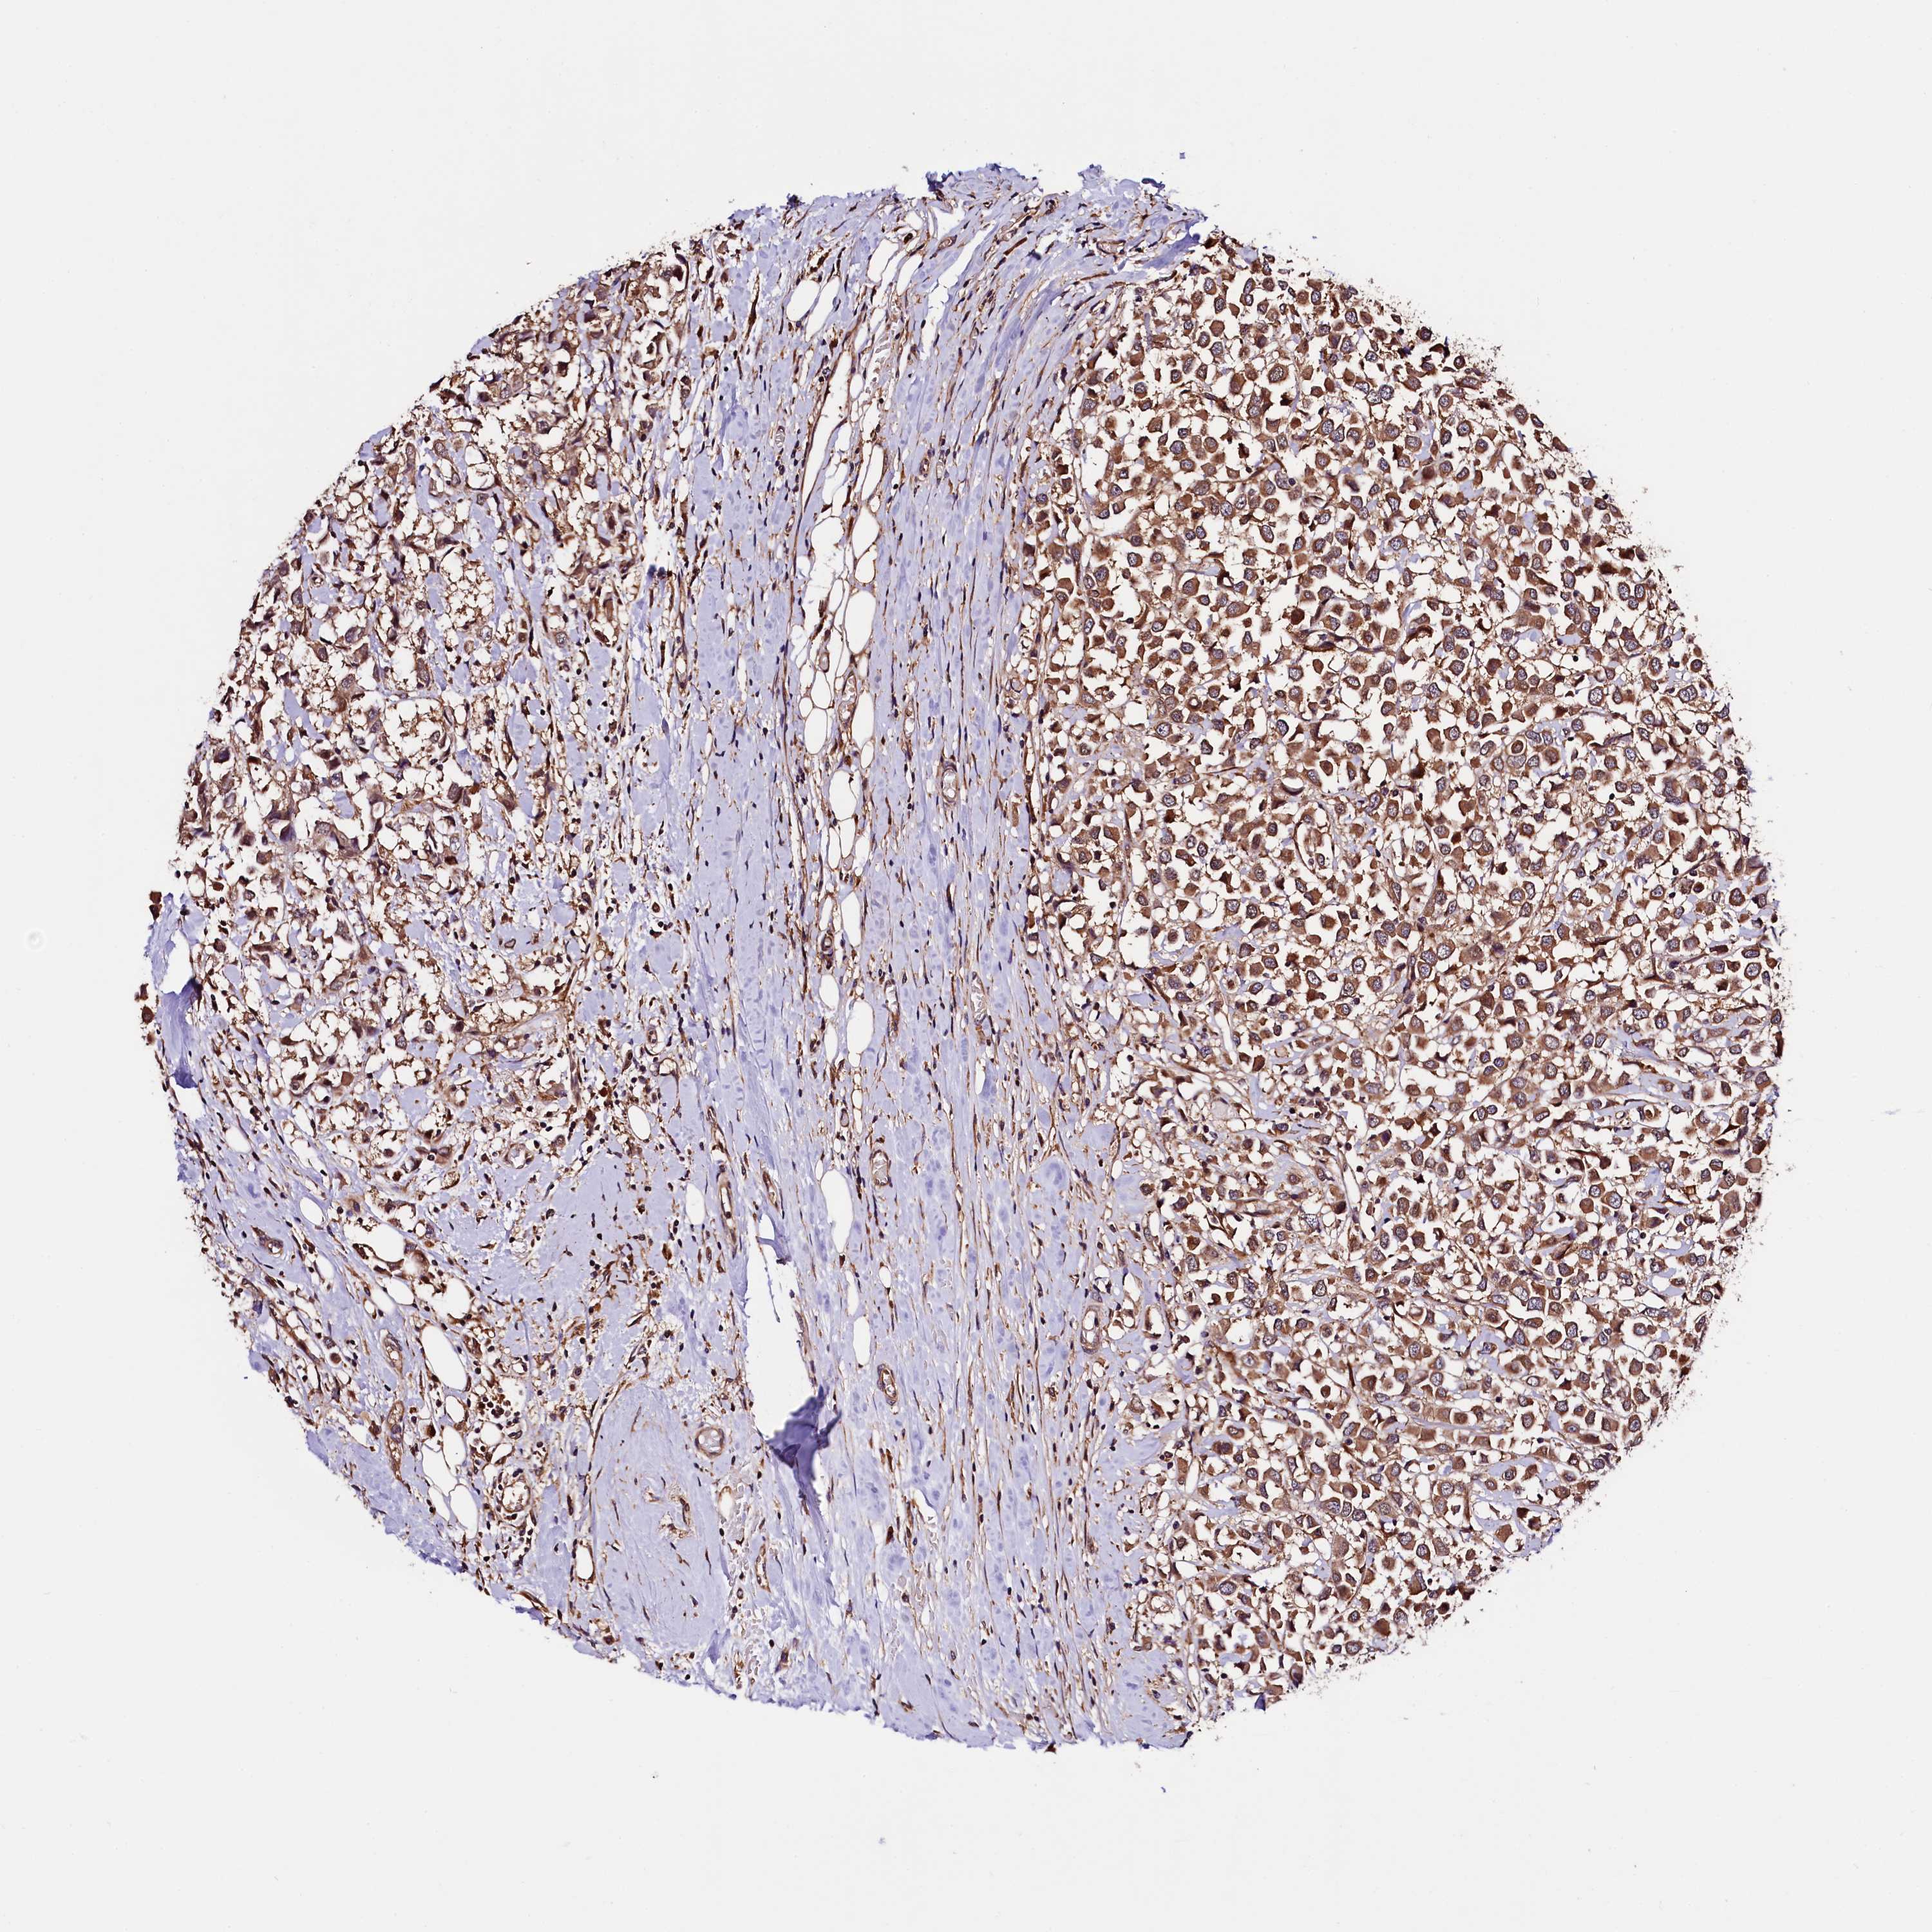

CANCER BREAST CANCER Show tissue menu

BRCA TCGA BRCA VALIDATION PROTEIN EXPRESSION